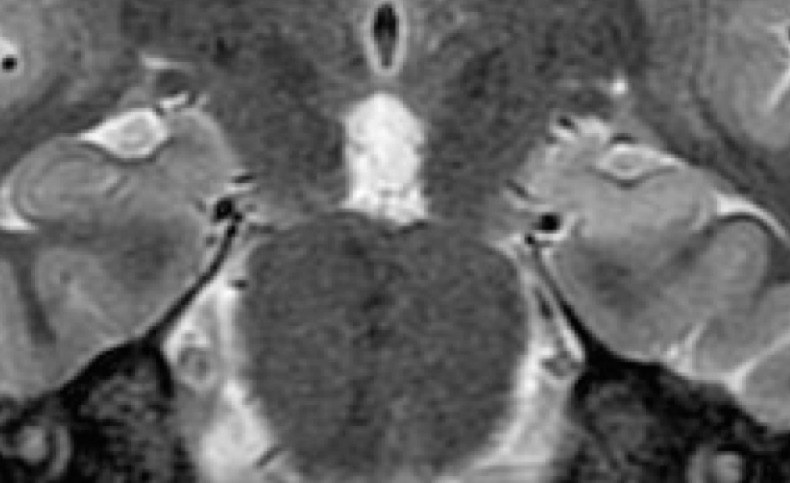

MRI (Magnetic Resonance Imaging)

Epilepsy treatment is most effective when the onset of the seizure can be specifically localized to one or more origins within the brain. MRI collects structural information and creates images of the brain by using a large magnet. It is the most important imaging modality for epilepsy evaluation. Because of its critical role in management, MRI should be performed using a state-of-the-art 3 tesla MRI scanner according to technically specific scan protocols. The MRI should also interpreted by subspecialty-certified neuroradiologists with expertise in epilepsy.